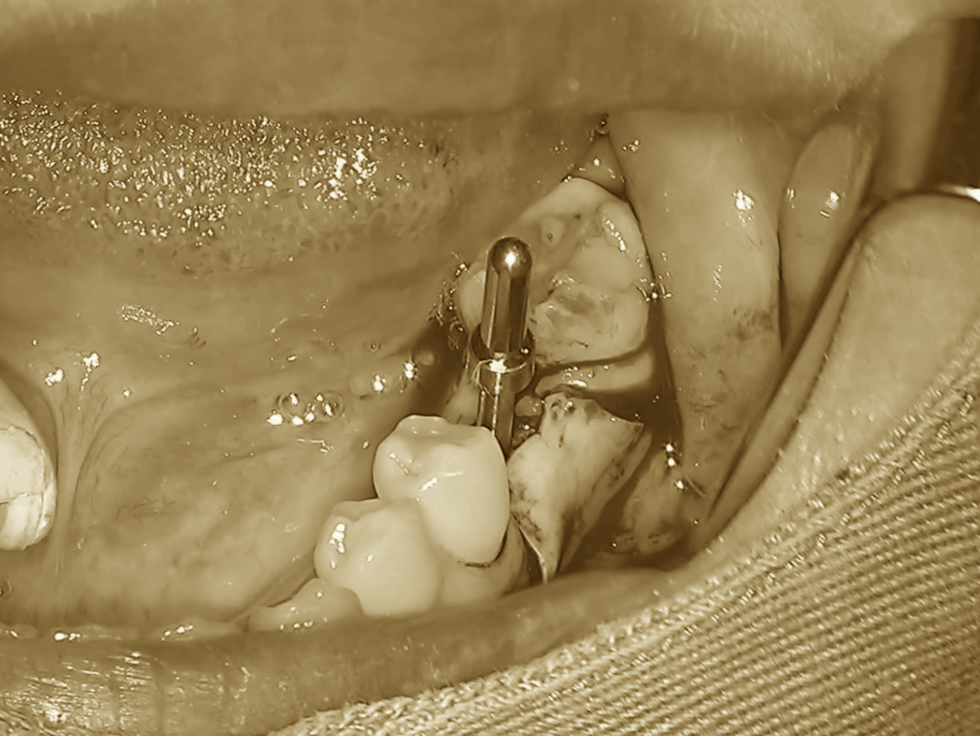

一度ドリルで形成した後、

方向確認用の器具を挿入し、

「狙った位置に正しく形成できているか」

を慎重にチェックします。

ここで当院の特徴でもあるポイントが一つあります。

それは、

低速回転かつ無注水でのドリリングを選択していることです。

そのため当院では、あえて

低速回転・無注水での切削を選択することがあります。

その理由はシンプルで、

「自家骨を採取するため」です。

骨を削った際に出てくる細かな骨片は、

そのまま非常に優れた再生材料として利用できます。